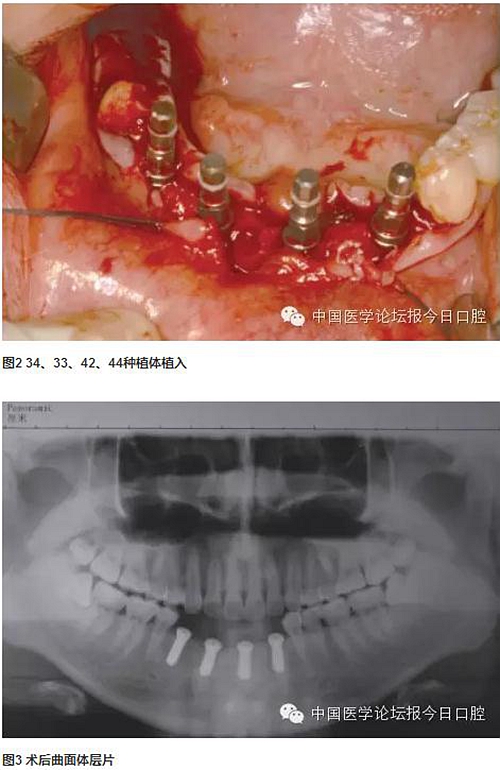

分別于下頜左側(cè)尖牙、下頜左側(cè)中切牙、下頜右側(cè)側(cè)切牙、下頜右側(cè)第一前磨牙位點植入4顆長度為10mm的常規(guī)頸種植體,3個月后取模制作研究蠟型,可見種植體開口方向均在舌側(cè),較適合制作螺絲固位修復(fù)體。兩次法取模,已釋放材料收縮應(yīng)力對取模的準(zhǔn)確性產(chǎn)生的影響,確保石膏模型上種植體位置準(zhǔn)確。

技工室制作純鈦支架,聚合瓷修復(fù)牙齒和牙齦形態(tài),患者口內(nèi)試戴,只將一個種植體的固定螺絲加力,拍片可見其余3顆種植體均實現(xiàn)被動就位,然后將4顆種植體固定螺絲加力,封口(圖2~圖10)。